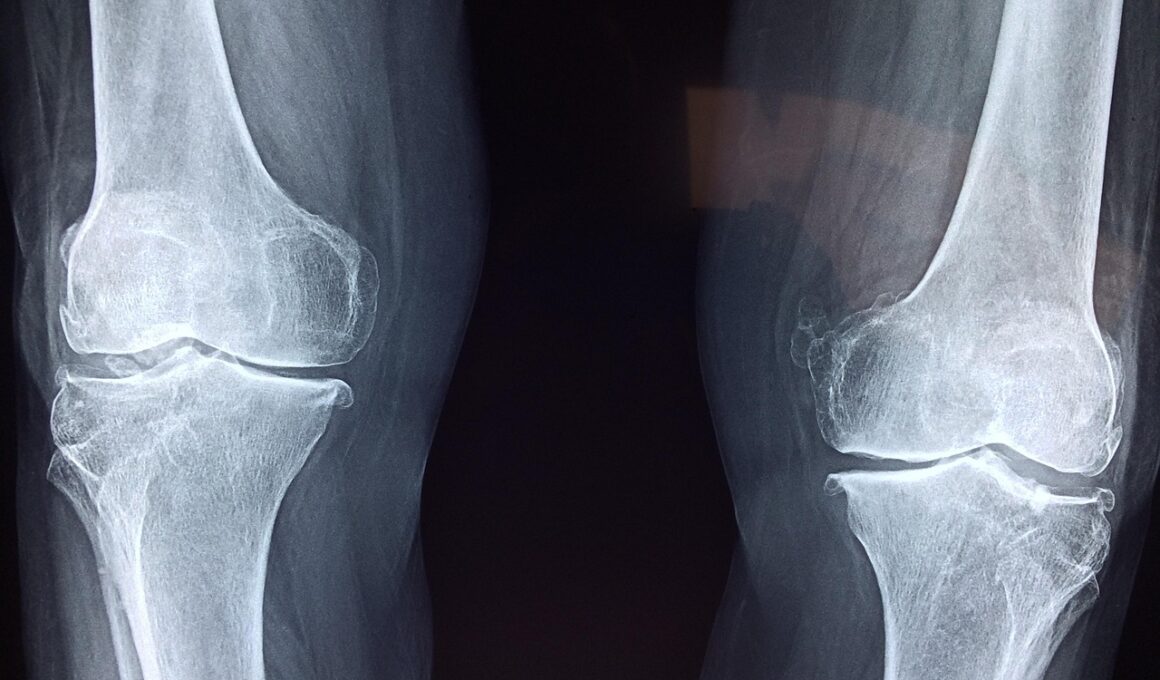

As athletes get older, joint health becomes an increasing concern. Factors like wear and tear, previous injuries, and diminished recovery capabilities contribute to joint pain and inflammation. Aging can lead to conditions like osteoarthritis, making it crucial for athletes to explore ways to maintain optimal joint function. Utilizing joint health supplements can aid in reducing discomfort and promoting mobility. These supplements often contain ingredients known for their anti-inflammatory properties and ability to support cartilage health. Before selecting a supplement, it’s essential to consider the ingredients and their dosages, ensuring they align with individual needs. The effectiveness may vary among different athletes due to varying body responses. Thus, members of the athletic community are often suggested to consult healthcare providers. This professional guidance allows athletes to choose the most effective resolutions. Alongside supplementation, a balanced diet and regular exercise specifically designed for joint support are integral components of a joint health strategy. Personalization in both nutrition and exercise regimens may yield the best results as athletes look to maintain performance levels while safeguarding joint integrity.

Joint health issues in aging athletes can compound over time, making proactive long-term strategies crucial. Preventative care becomes vital; focusing on joint health means implementing measures to maintain mobility and flexibility throughout an athlete’s career. Regular check-ups with health professionals aid in monitoring joint conditions and adapting supplementation and exercise plans as needed. Furthermore, fostering an awareness of individual limits enhances safety and prevents injuries that can lead to chronic joint issues. Athletes should meticulously listen to their bodies during physical activities to avoid overexerting themselves. Recovery practices, including effective stretching and rest, are equally essential. Implementing non-invasive therapies, such as ice therapy or compression, can facilitate healing and reduce inflammation after strenuous workouts. Integrating mind-body practices such as mindfulness or meditation can further improve the overall lifestyle and mental aspect of facing aging challenges. By adopting holistic approaches that encompass both physical and mental wellbeing, aging athletes can create a sustainable routine that supports their joint health and overall vitality.